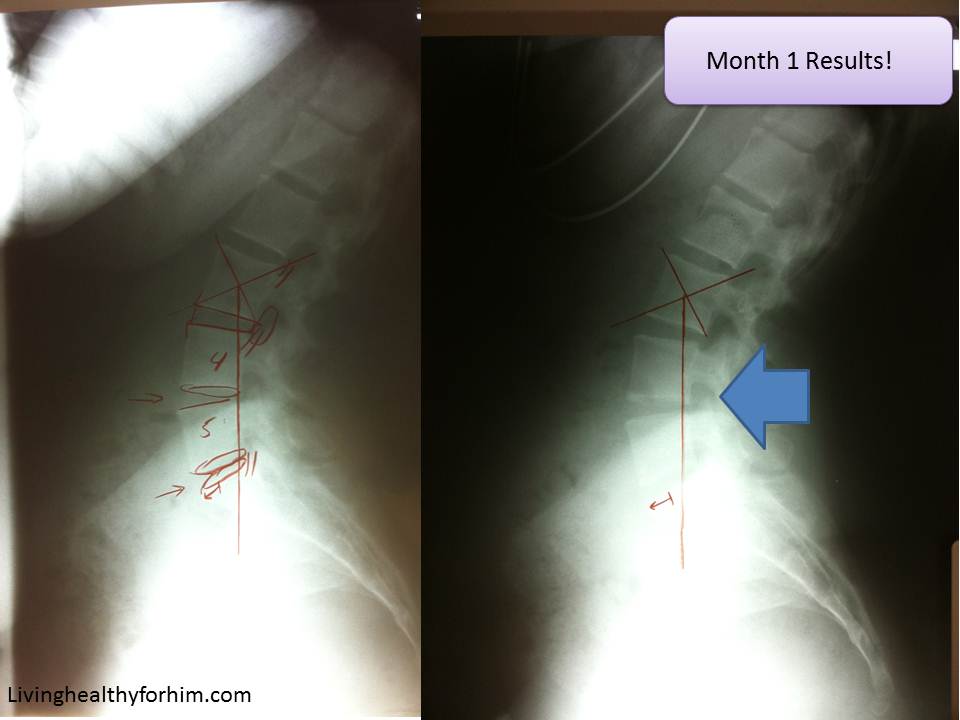

Now my neck has a different story to tell. It is making progress, but with it comes a price. First, looking at the initial x-ray on the left, you can see that my neck is curving the complete opposite way from the normal C shape that the neck should have. But in my second x-ray, you can see it is ever so slowly trying to curve the correct way. Come on cervical vertebrae! You can do it!